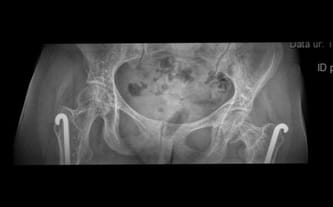

Powyżej zdjęcie, na którym widać pogłębienie szpotawości biodra lewego, co za tym idzie, noga staje się krótsza. Aktualnie czekam na konsultacje w Łodzi z panią profesor, po której ma być wdrożone leczenie osteoporozy zastrzykami, które zakwalifikują mnie do zabiegu.

Na RTG kręgosłupa widać dużą ilość cementu wylanego poza obszar kręgosłupa. Z kolei na drugim zdjęciu widać czubek pręta Rusha. Niestety, nastąpiła szpotawość biodra lewego, co skutkuje stanem zapalnym w obrębie pręta. Wiąże się to z codziennym, ogromny bólem. Do kolejnych problemów dochodzą zmiany zwyrodnieniowe w kręgosłupie. Lekarze rozkładają ręce…